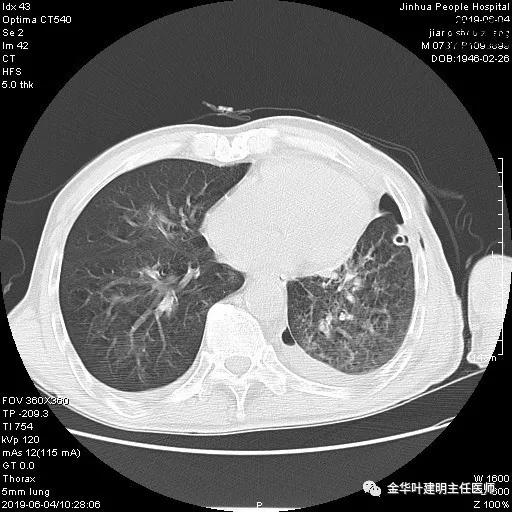

6.4上午:24小时引流出血性乳糜液1800毫升。是否再次手术进行右进胸胸导管结扎,抑或继续保守治疗非常纠结!压力非常大!!多方讨论会诊无法取得一致意见,但一般认为,引流量在1000毫升以上宜积极手术。情况与浙二医院范军强教授联系,请求指导,范教授认为左侧肺手术,损伤胸导管主干的机会较小,多数可保守治疗而愈。在他们的病例中,也有结扎胸导管后引流量仍无减少,效果并不能完全保证。建议可以斟酌胸管夹管观察(因为淋巴管压力低,予以适当的压力,漏出量可能会明显减少),同时继续禁食,并静脉营养支持,引流管口可能会有渗液,注意更换敷料。与家属充分沟通后决定试夹管;这天血色素9.0 g/L;胸部CT复查示:

夹管情况下,于6.5复查胸片:

感觉左肺密度还可以,肺没有被全部压萎陷,积液有,但不是特别多。